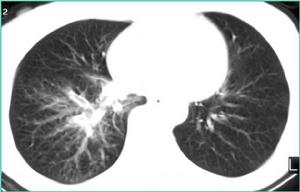

X線檢查

早期可無明顯改變,反覆急性發作者可見兩肺紋理增粗、紊亂呈網狀或條索狀及斑點狀,陰影以下肺野為明顯,此系由於支氣管管壁增厚、細支氣管或肺泡間質炎症細胞浸潤或纖維化所致。